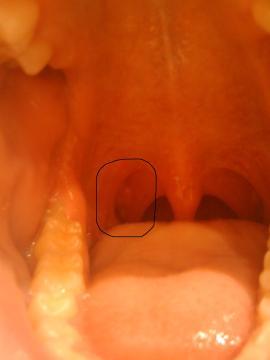

Dobrý den, před cca měsícem jsem si všimnul nad pravou mandlí (na zadním oblouku jí ohraničující) 2-3 růžových útvarů podoby rýže. Nijak to nebolí, ale také nemizí (nad levou mandlí podobné a menší útvary zmizely). Chtěl bych se Vás zeptat zda může jít o nějakou bakteriální infekci? Před cca měsícem a půl jsem měl opakovaně zvýšené hodnoty štítné žlázy (T4) ale TSH v normě, po měsíci se stav hormonů spontánně upravil, výsledek pravděpodobně prodělaný zánět štítné žlázy. Děkuji Vám mnohokrát za odpověď.

Pravděpodobně se jedná o čepy na mandlích, které se objevují v souvislosti se záněty mandlí. Doporučím Vám navštívit ORL lékaře.